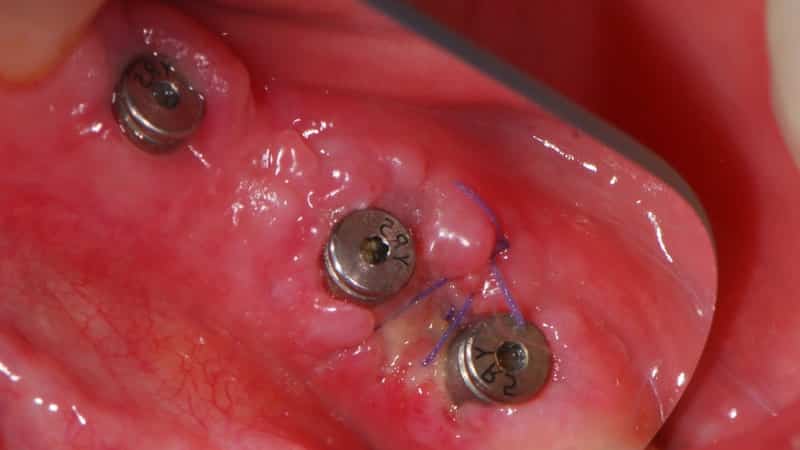

Сначала осуществляется анестезия, чтобы минимизировать дискомфорт пациента. Затем хирург делает небольшой разрез в десне, чтобы получить доступ к имплантату. После этого формирователь десны устанавливается на имплантат, и десна аккуратно обрабатывается вокруг него. Важно, чтобы формирователь был установлен правильно, так как это влияет на формирование десневого контура.

После установки формирователя десны, хирург закрывает разрез, используя швы, которые могут быть как рассасывающимися, так и нерассасывающимися. Время заживления после установки формирователя может варьироваться, но обычно составляет от одной до нескольких недель. В этот период важно следить за состоянием десен и соблюдать рекомендации врача по уходу за полостью рта.